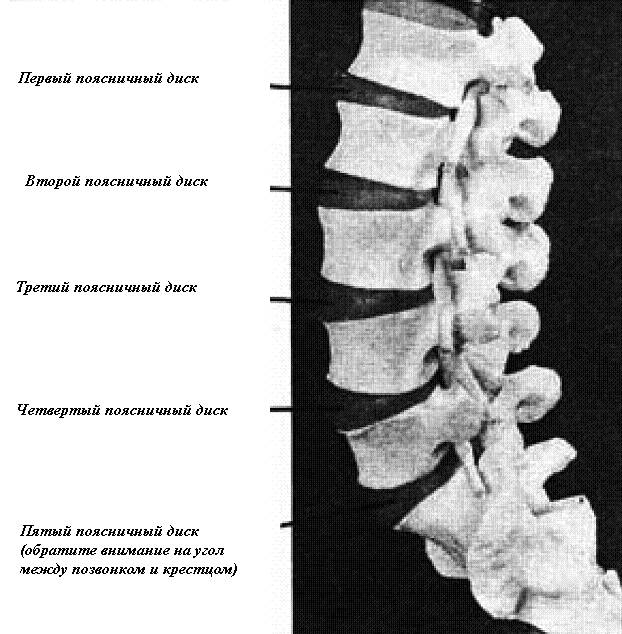

Помните, что хорошая осанка способствует сохранению мягких тканей крепкими, а переднего межпозвонкового пространства открытым, так что диски могут выполнять свою роль эффективных клиньев между позвонками (рис. 24).

Рис. 24. На модели поясничных позвонков видны раскрытые передние межпозвонковые пространства и часть нижнего изгиба позвоночника